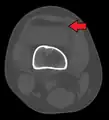

3D reconstruction of a CT image of a tibial plateau fracture